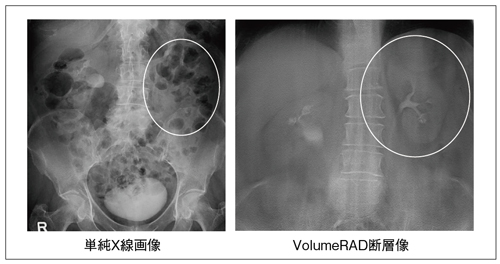

Discovery XR650におけるトモシンセシスの技術と特長 ─一般撮影,

Discovery XR650におけるトモシンセシスの技術と特長 ─一般撮影, 一般撮影システム RADspeed Pro™ style edition Fluoro Class,

一般撮影システム RADspeed Pro™ style edition Fluoro Class, Discovery XR650におけるトモシンセシスの技術と特長 ─一般撮影,

Discovery XR650におけるトモシンセシスの技術と特長 ─一般撮影, 島津製作所、動画とワイヤレス静止画撮影ができるFPD搭載の,